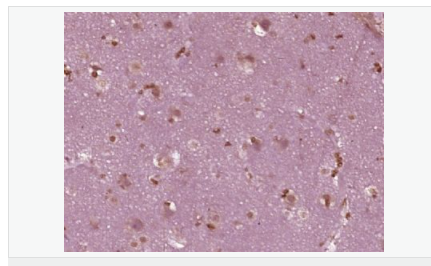

交叉反應(yīng):Rat,Mouse,Human(predicted:Sheep,Rabbit,Horse,Cow,Pig) 推薦應(yīng)用:IHC-P,ELISA

| 產(chǎn)品應(yīng)用 | ELISA=1:5000-10000 IHC-P=1:100-500 (石蠟切片需做抗原修復(fù)) not yet tested in other applications. optimal dilutions/concentrations should be determined by the end user. |